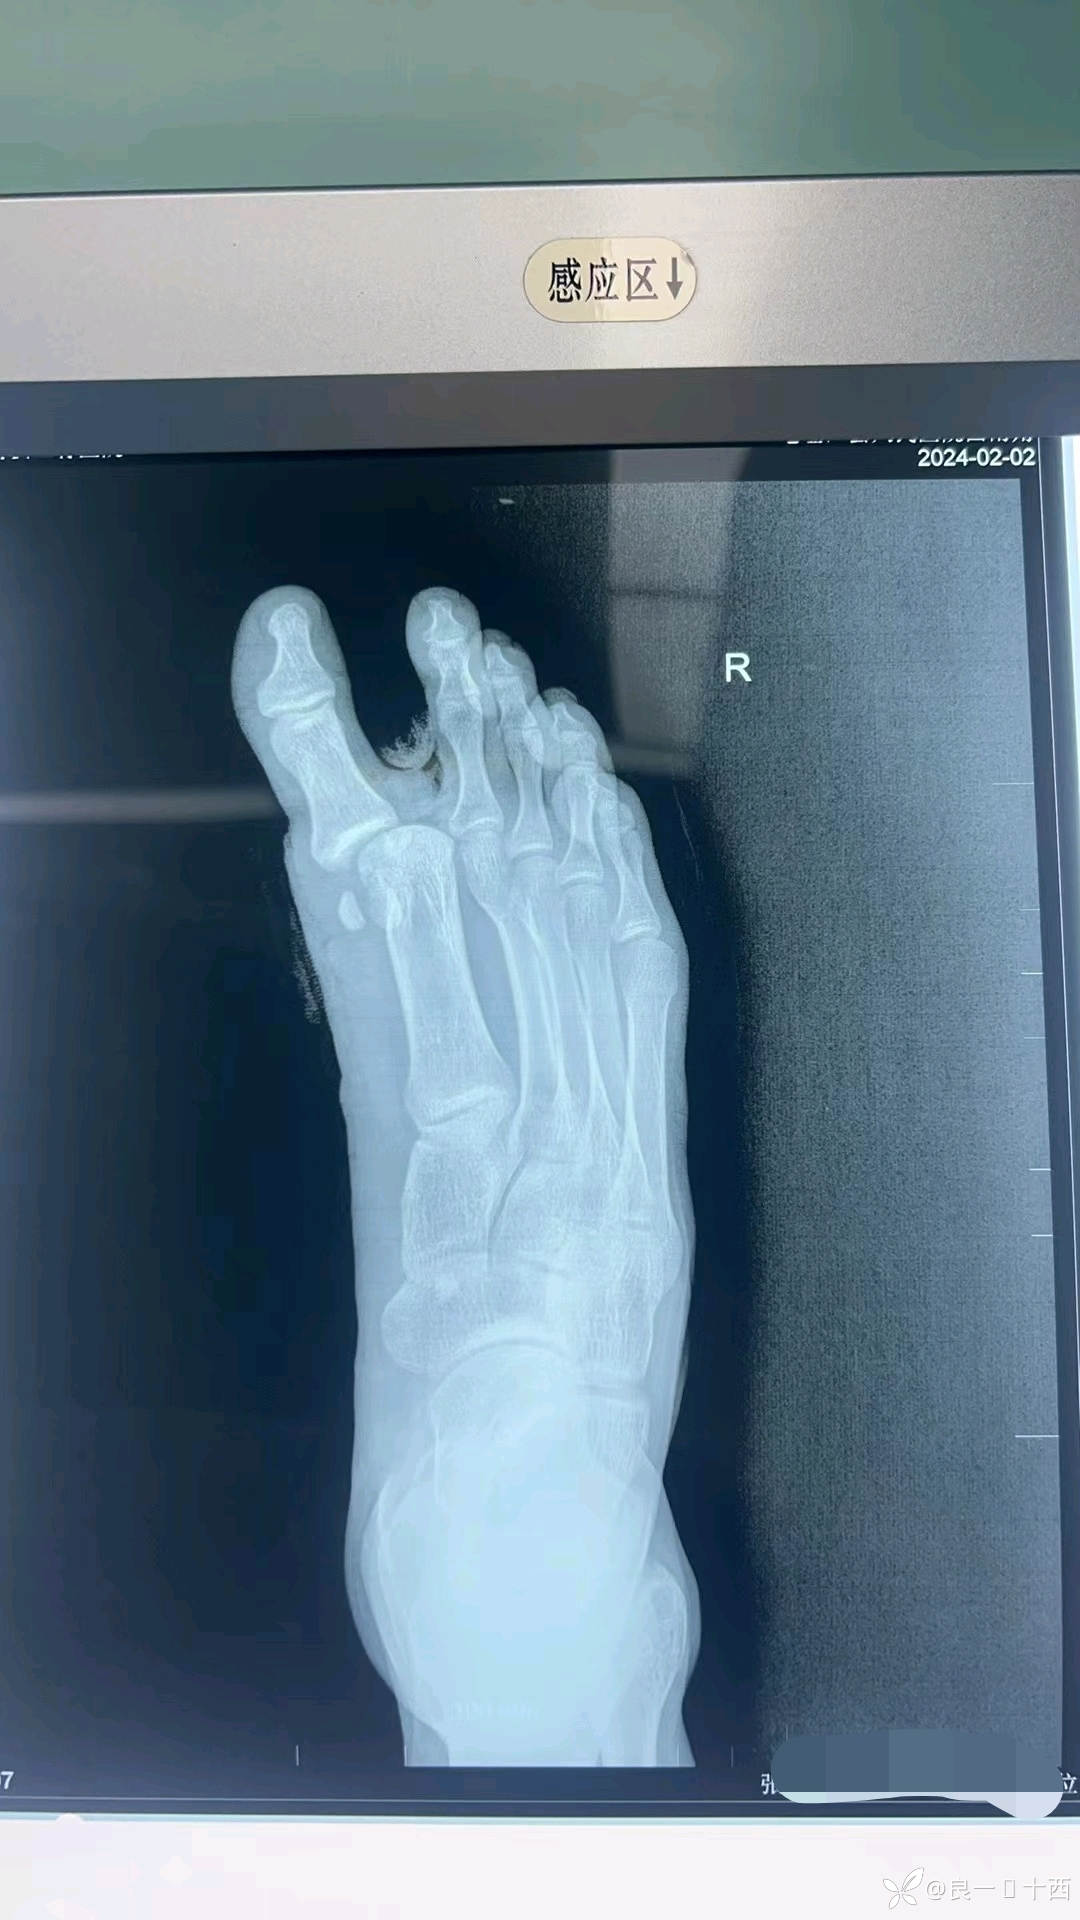

一位18岁帅气少年,应该是晚上通宵上网了,回来时候精神状态不佳,导致自己骑车出了车祸。初步检查后,得出诊断如下,右足拇趾基底部开放性撕脱骨折,拇收肌横头撕脱,第一跖趾关节开放性脱位,第二跖骨头开放性骨折,右足背内侧撕脱伤